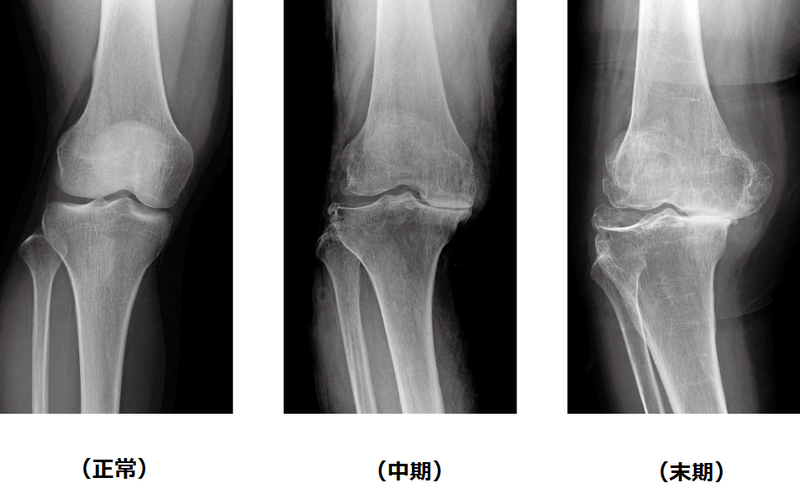

変形性膝関節症は初期、中期、末期に分類されます。

初期では動作時に膝の痛みを感じますが、しばらく休むと痛みが軽減します。中期では正座や階段昇降で膝に疼みを生じ、水が溜まります。